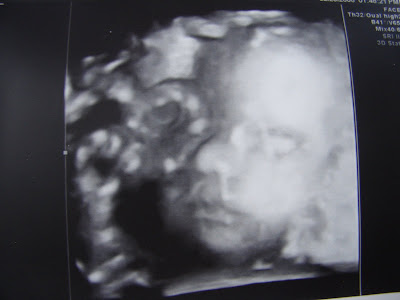

Through the miracle of modern technology, you can now see your baby, in utero, in three dimensions. Which is to say, you can see a teeny little baby with a teeny little face and teeny little hands all curled up and totally beyond fetal in his teeny adorableness while he is still tucked away deep inside your lady parts.

Also, however, you can see your own umbilical cord, pressing against his face like some sort of intra-uterine alien life form that might just develop a consciousness and a will of its own and creep out of your nether regions and strangle you in the night. Which, you know, is disturbing. No more disturbing that some of those pregnancy dreams that can sneak up on you, I suppose, but still (am I the only who has had nightmares about nursing mutant kittens? No? Never mind). Maybe there’s too much information that comes with being able to get a three-dimensional glimpse inside one’s own uterus.

That said: LOOK AT MY TEENY-WEENY WIDDLE SPROUT WITH HIS ITTY-BITTY LITTLE HAND AND HIS PRECIOUS LITTLE MOUTH OMG!